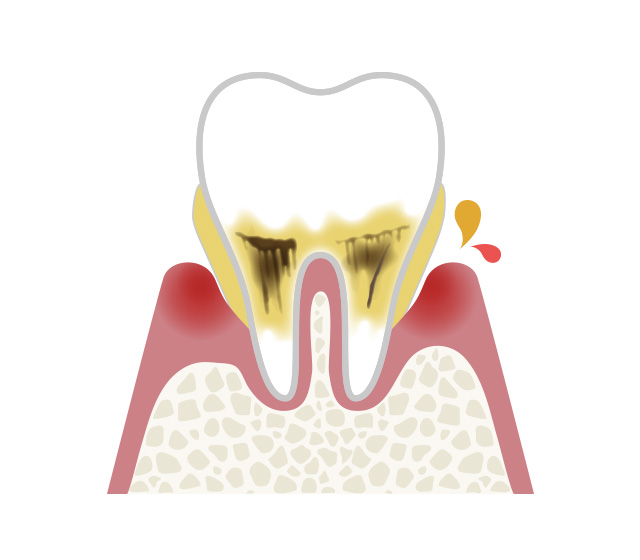

歯ぐきから血が出ていないから大丈夫と思われているかもしれませんが、歯周病は血が出ていなくても進行しています。歯周病はサイレントキラーと呼ばれるほど自覚症状がなく進行してく病気です。

その背景にも関連し、知らず知らずのうちに歯周病が進行し、日本の成人では約80%が歯周病にかかっていると言われています。

歯周病のこと~日本人の80%は歯周病です~